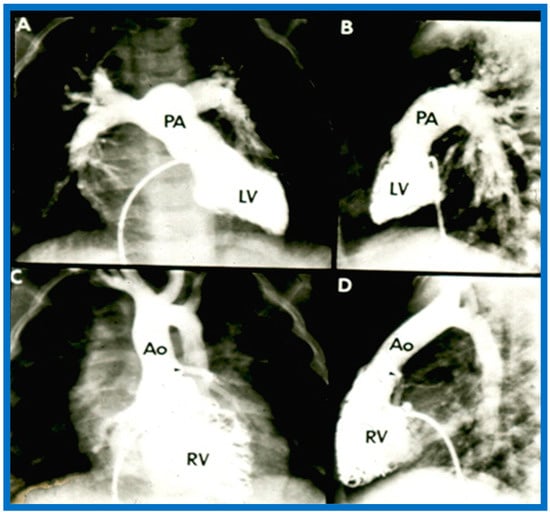

Figure 31. Selected angiographic images demonstrating characteristic features of the right (A) and left (B) ventricles. The right ventricle (RV) exhibits coarse trabeculations (A), while the left ventricle (LV) shows smooth or fine trabeculations (B). In addition, the RV exhibits a triangular shape, whereas the LV is a foot-shaped structure. The tricuspid (TV) and pulmonary (PV) valves (arrows in (A)) are separated by a muscular structure, crista supraventricularis. Aorta (Ao) and pulmonary artery (PA) are labeled. Modified from reference [3].

Ventricular Trabeculations and Shape

The morphologic LV is a smooth-walled structure with fine trabeculations and a foot-shaped appearance, whereas the morphologic RV has coarse trabeculations and a triangular shape. These features are demonstrated by echocardiographic (Figure 34) and angiographic (Figure 31, Figure 35 and Figure 36) studies. It should be noted that the characteristic trabecular pattern of the ventricles is seen irrespective of great vessel relationship: normally related great vessels (Figure 31 and Figure 34), transposed great arteries in levocardia (Figure 35) or transposed great arteries in dextrocardia (Figure 36).

Figure 35. (A,B). Selected cine frames of the Left ventricle (LV) in posteroanterior (A) and lateral (B) projections of a child with d-transposition of the great arteries illustrating morphologic LV with fine trabeculations. The pulmonary artery (PA) originates from the LV. The pulmonary valve is positioned inferior and posterior to its normal position. (C,D). Selected cine frames of the right ventricle (RV) in posteroanterior (C) and lateral (D) projections of the same child shown in (A,B) illustrating morphologic RV with coarse trabeculations. The aorta (Ao) originates from the RV. The aortic valve is positioned superior and anterior (C,D) to its normal position. The closeness of the mitral with the pulmonary valve in a morphologic LV (A,B) and the separation of tricuspid and aortic valves in a morphologic RV (particularly in D) is clearly seen. Replicated from reference [35].

Figure 36. (A) Cine frame from morphologic left ventricular (MLV) cineangiogram in a posteroanterior view of an infant with dextrocardia, exhibiting fine trabeculations of the MLV on the left side. The MLV gives origin to the main pulmonary artery (MPA), which is dilated. The position of the catheter in the inferior vena cava (IVC) is on the left side of the spine. (B) Demonstrates a morphologic right ventricle (MRV) in a posteroanterior view in the infant shown in (A); coarse trabeculations are seen. The right-sided MRV gives rise to the aorta, denoted by AAo. The aorta descends on the right side of the spine. The aortic valve is situated rightward and superior to the pulmonary valve. It is located anteriorly in the lateral view (not shown). This information suggests a d-loop of the ventricles and d-transposition of the great arteries in a subject with dextrocardia, a disorder suggestive of corrected transposition physiology. DAo, descending aorta. Replicated from reference [36].